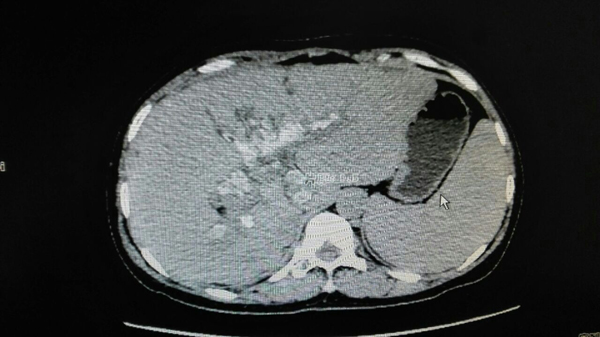

• 男子二十余年不患病 一病便是巨大肝癌——我院第二例二步肝癌切除术(ALPPS术)成功完成

男子二十余年不患病 一病便是巨大肝癌——我院第二例二...

突然接到电话说我哥住院了,觉得非常不可思议!十多天后,粱先生的小弟还对哥哥突然生病一事很疑惑。 因二十几年没有生过病,突然就住院了,...